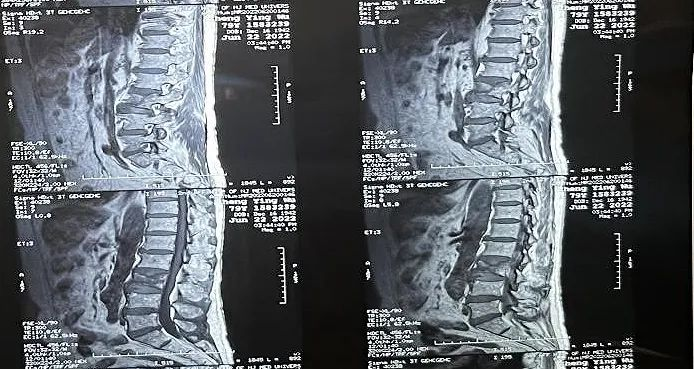

臨床手術過程

術中切口5毫米,在大平板C臂機的透視指引下,確定了進針的方向及進針的深度。經椎弓根向椎體置管,建立通道,插入骨擴張器(球囊)。球囊擴張恢復椎體高度,并在椎體內形成空腔,確定骨水泥的注入劑量,并注入骨水泥觀察其擴散情況。